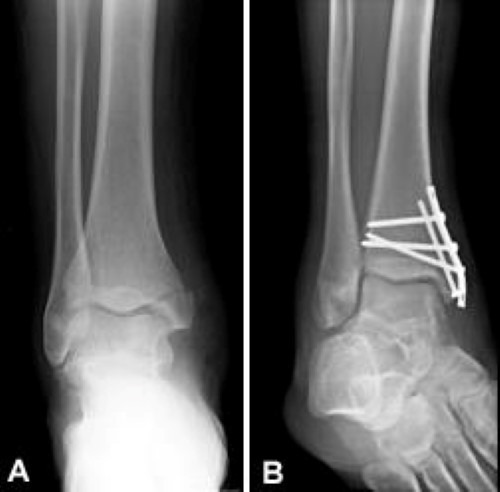

Home » » Maleolus / Ankle Fracture Surgery Dr Neal Blitz New York Nyc -

Maleolus / Ankle Fracture Surgery Dr Neal Blitz New York Nyc -